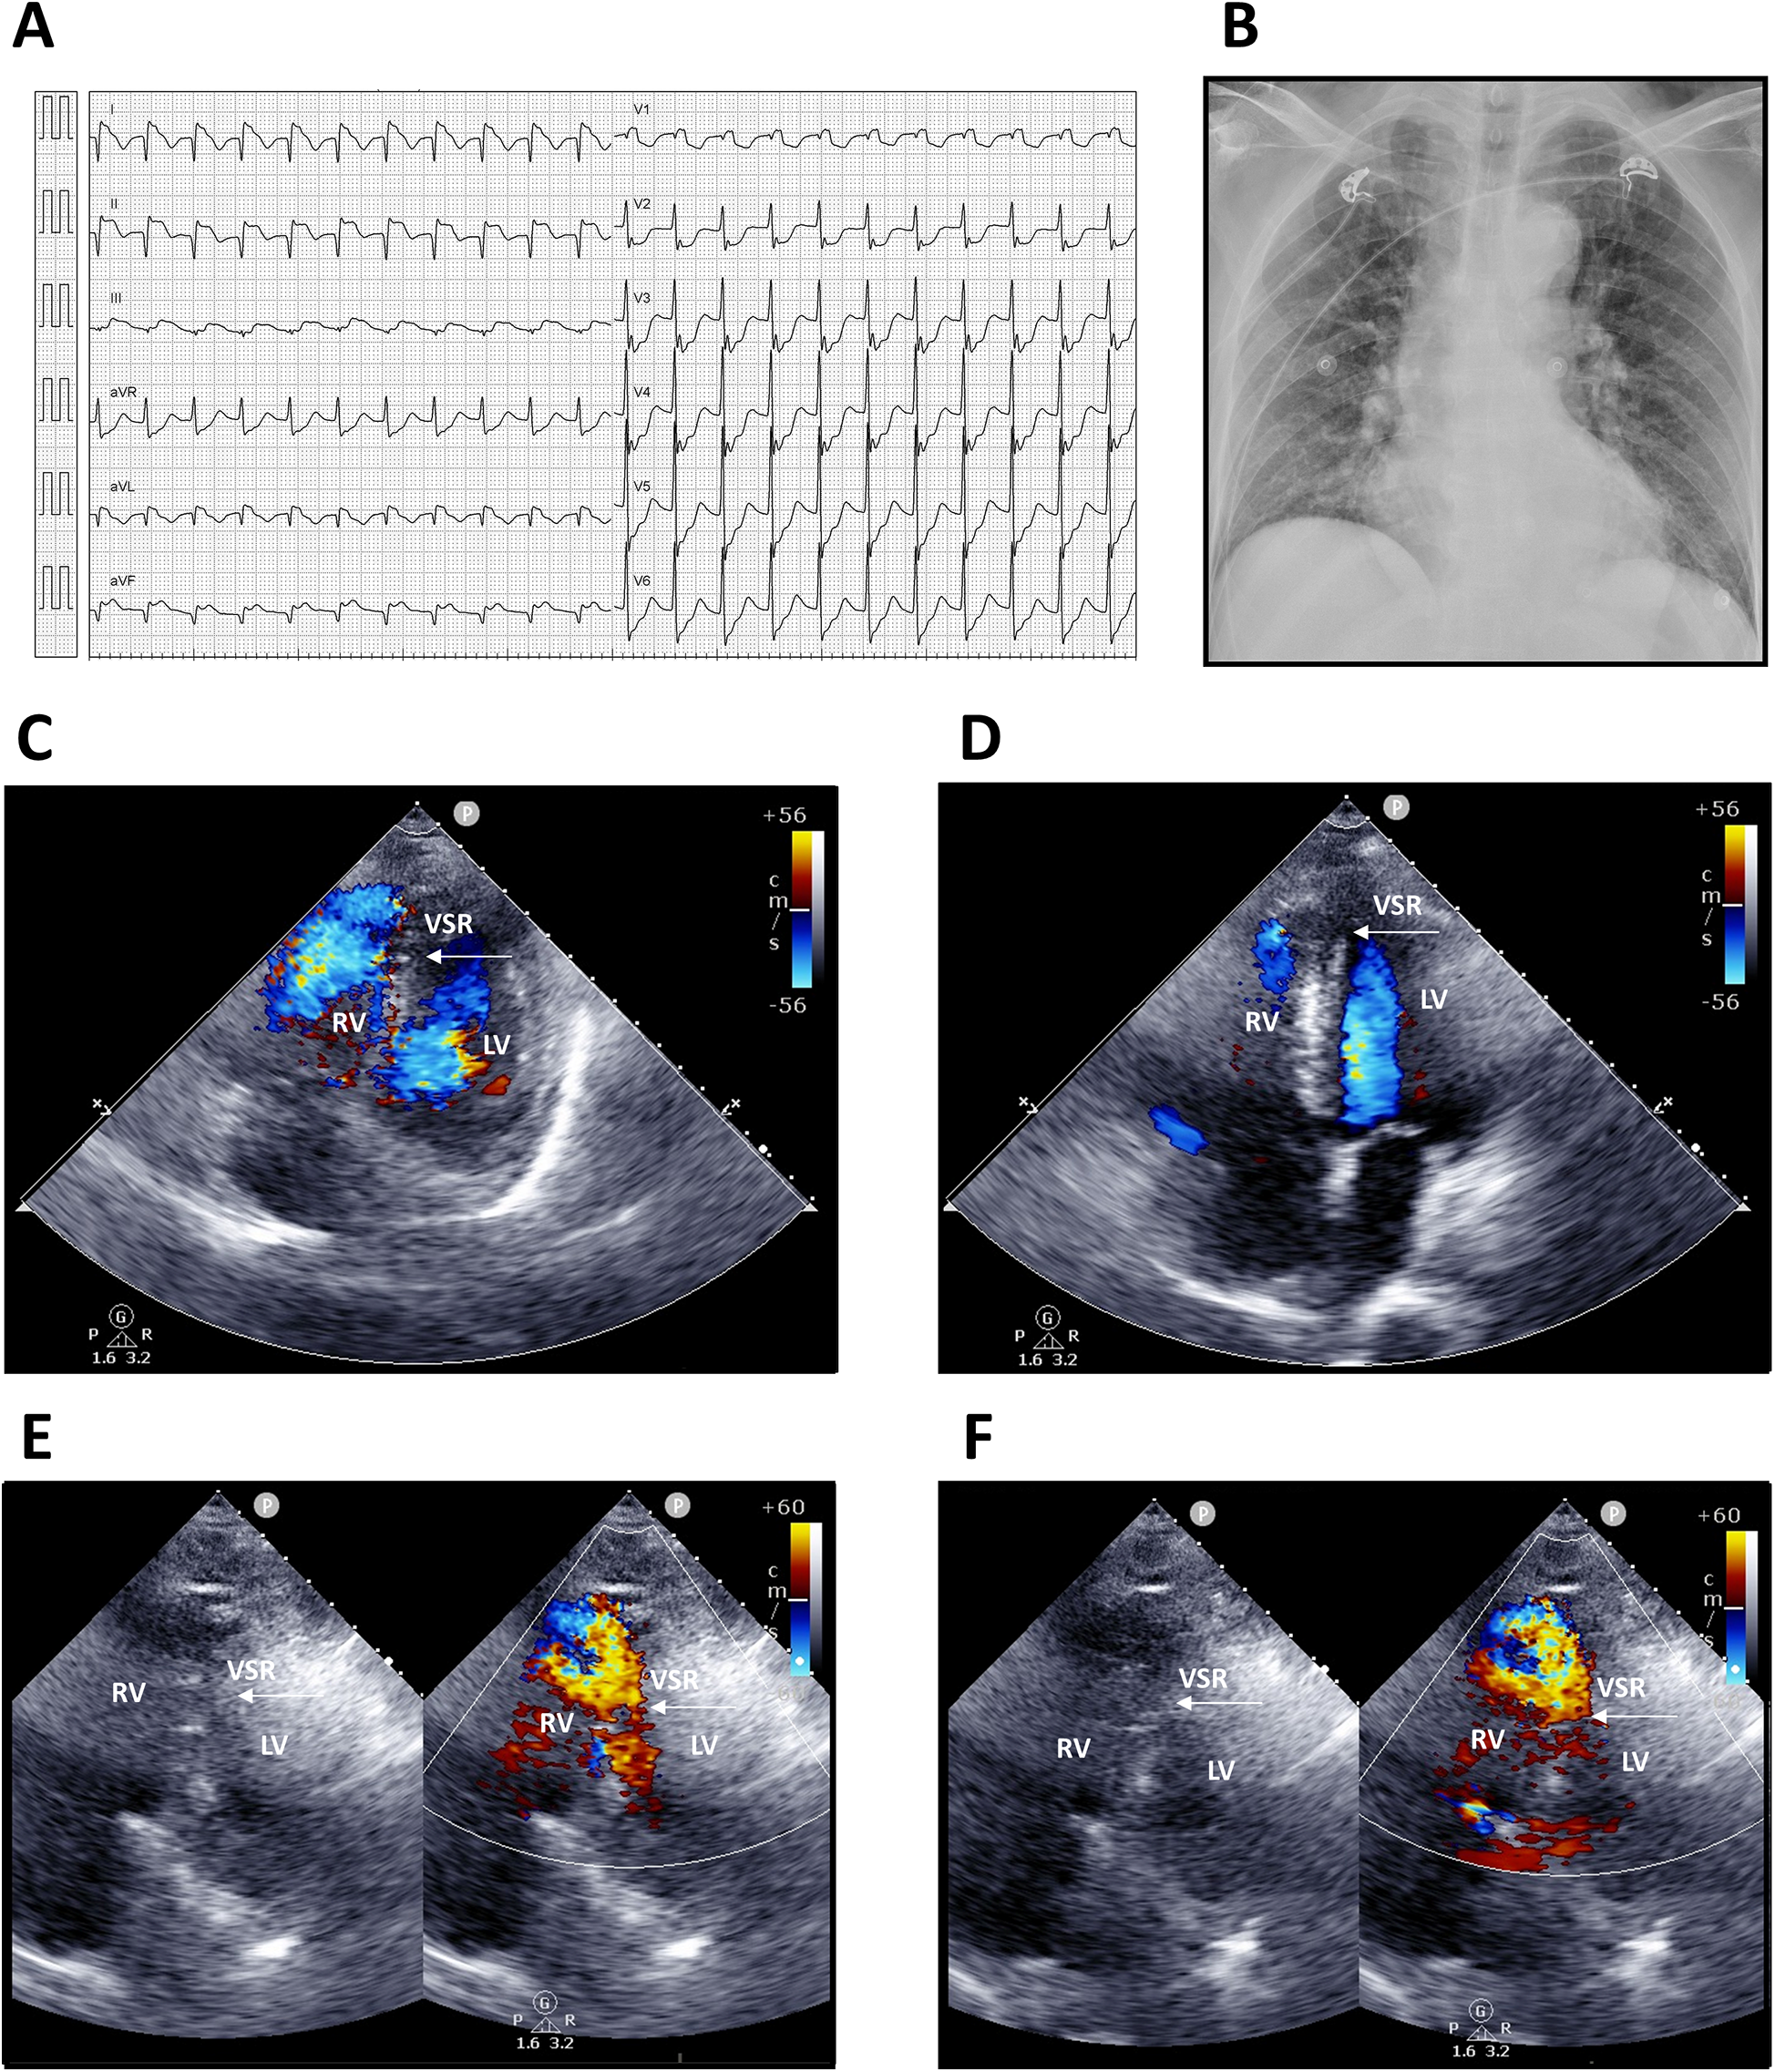

Upon arrival, he was conscious but in shock, with vital signs showing blood pressure 68/48 mmHg, heart rate 136 bpm, respiratory rate 20/min, and body temperature 35.4°C. Physical examination revealed a grade 3/6 pansystolic murmur along the left sternal border, with clear breath sounds. Laboratory findings demonstrated leukocytosis [white blood count (WBC) 12,150/µL, segmented neutrophils 95.8%] and elevated troponin-I (9.873 ng/mL). Electrocardiography showed supraventricular tachycardia, complete right bundle branch block (CRBBB); ST-segment elevation in leads I, II, and aVF (reversed arm leads); and ST-segment depression in V2–6 (Figure 1A). An acute inferior wall ST-elevation myocardial infarction was suspected. Chest radiography revealed right ventricular enlargement and pulmonary plethora (Figure 1B). Based on these findings, an acute inferior STEMI was diagnosed. Aspirin, ticagrelor, and intravenous heparin were administered.

Figure 1

Electrocardiography, chest radiography, and transthoracic echocardiography findings. (A) Twelve-lead electrocardiogram showing supraventricular tachycardia 130 bpm; incomplete right bundle branch block (ICRBBB); ST-segment elevation in leads I, II, and aVF (suspected reversed arm leads); and ST-segment depression in V2–6. (B) Chest radiograph demonstrating right ventricular enlargement and pulmonary arterial plethora. (C,D) Apical four-chamber views. (E,F) Modified apical four-chamber views with two-dimensional and color Doppler imaging, revealing a large rupture of the inferior–posterior interventricular septum (arrows) with a significant left-to-right shunt. LV, left ventricle; RV, right ventricle; VSR, ventricular septal rupture.

Transthoracic echocardiography suggested distal interventricular septum rupture with a left-to-right shunt (Figures 1C–F). Intravenous normal saline was given for hypotension, and the patient underwent emergency coronary angiography, which revealed total occlusion of the middle right coronary artery. Balloon angioplasty with bare-metal stenting was performed (Figures 2A,B; Supplementary Videos S1–S6). Left ventriculography confirmed a large rupture in the posterior inferior interventricular septum with significant left-to-right shunting (Figures 2C–F; Supplementary Videos S7, S8). VA-ECMO was initiated for hemodynamic stabilization, after which he was admitted to the intensive care unit (ICU). Informed consent for surgical intervention was obtained from his family.